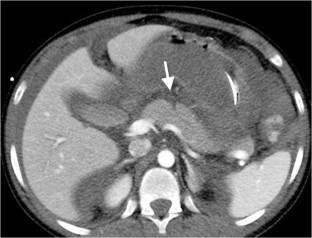

Of 3,265 patients presented as trauma team activations during the study period, only 28 (0.86%) children (19 boys, 9 girls; mean age: 7.14 years; age range: 1–15 years) had pancreatic injury. Of the available 27 CTs of the abdomen, 26 were performed on the day of trauma. Associated injuries were seen in 25/27 children, most frequently in the liver and lung, 16 (59.2%) each. There were 5 (19%) Grade I, 9 (33%) Grade II, 8 (30%) Grade III and 3 (11%) Grade IV. No patients had Grade V injury. No pancreatic parenchymal injury was identified in 2 (7%) patients with isolated fluid around the pancreas and mesentery. The pancreatic duct was visible in all 10 children (days: 0–330, median days: 41 post-trauma) who had MRI. Eight of these children, who had Grade III/IV injuries on CT and confirmed pancreatic duct injury on endoscopic retrograde cholangiopancreatography (ERCP) or surgery, showed either signal intensity difference in pancreatic parenchyma and/or caliber difference in the pancreatic duct proximal and distal to the injury site. Two patients died because of multiorgan injuries, 9 patients (mainly with Grade III and IV injuries) underwent surgery and/or ERCP, and 16 patients were managed conservatively. AAST grading of pancreatic injury on CT correlated with type of management (P=0.0001) with most of the Grade III and IV injuries treated with intervention and/or surgery while all of the Grade I and II injuries were treated conservatively.

Pancreatic injury is rare in children but often associated with other organ injuries most frequently involving the liver and lung. CT grading of injury correlates with management and guides intervention and/or surgery versus conservative treatment. MRI is useful for assessing pancreatic duct injury by demonstrating the pancreatic duct directly and/or secondary changes like signal intensity difference in pancreatic parenchyma and caliber difference in the pancreatic duct.

Fig. 2